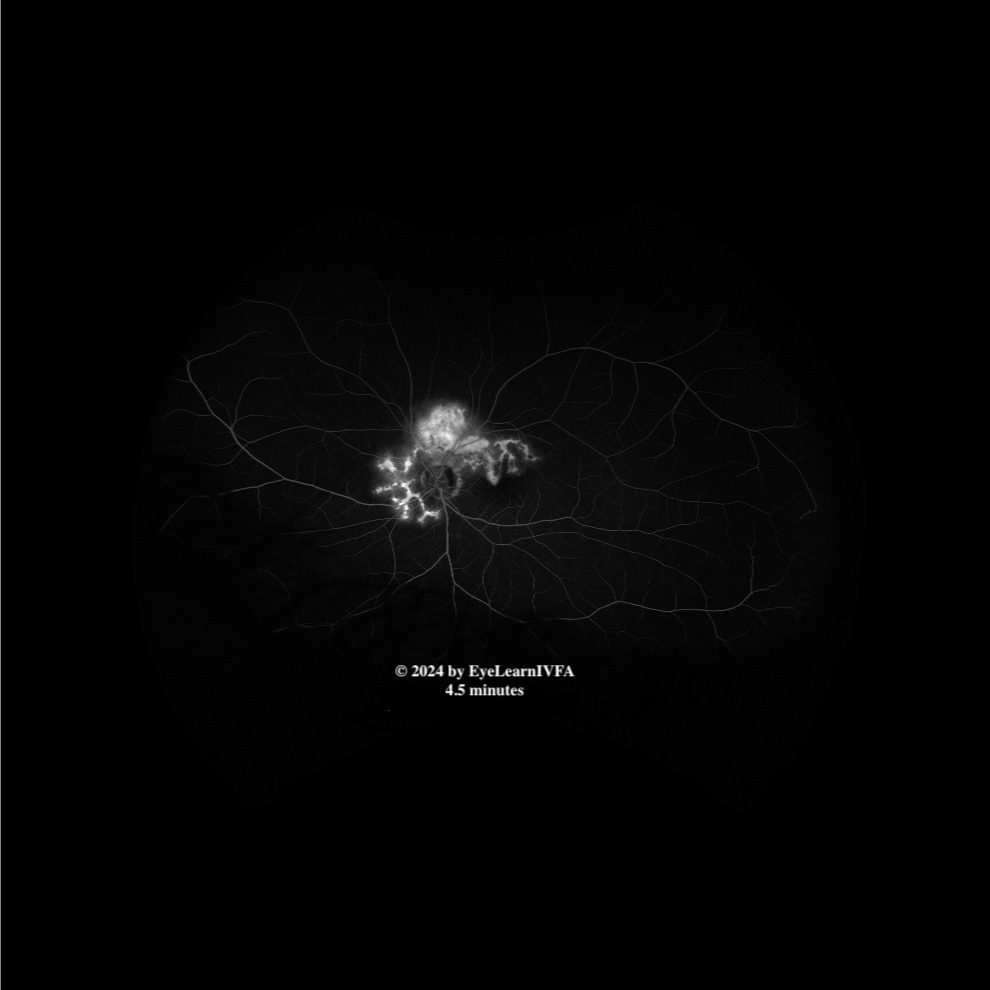

Uveitis Case #1